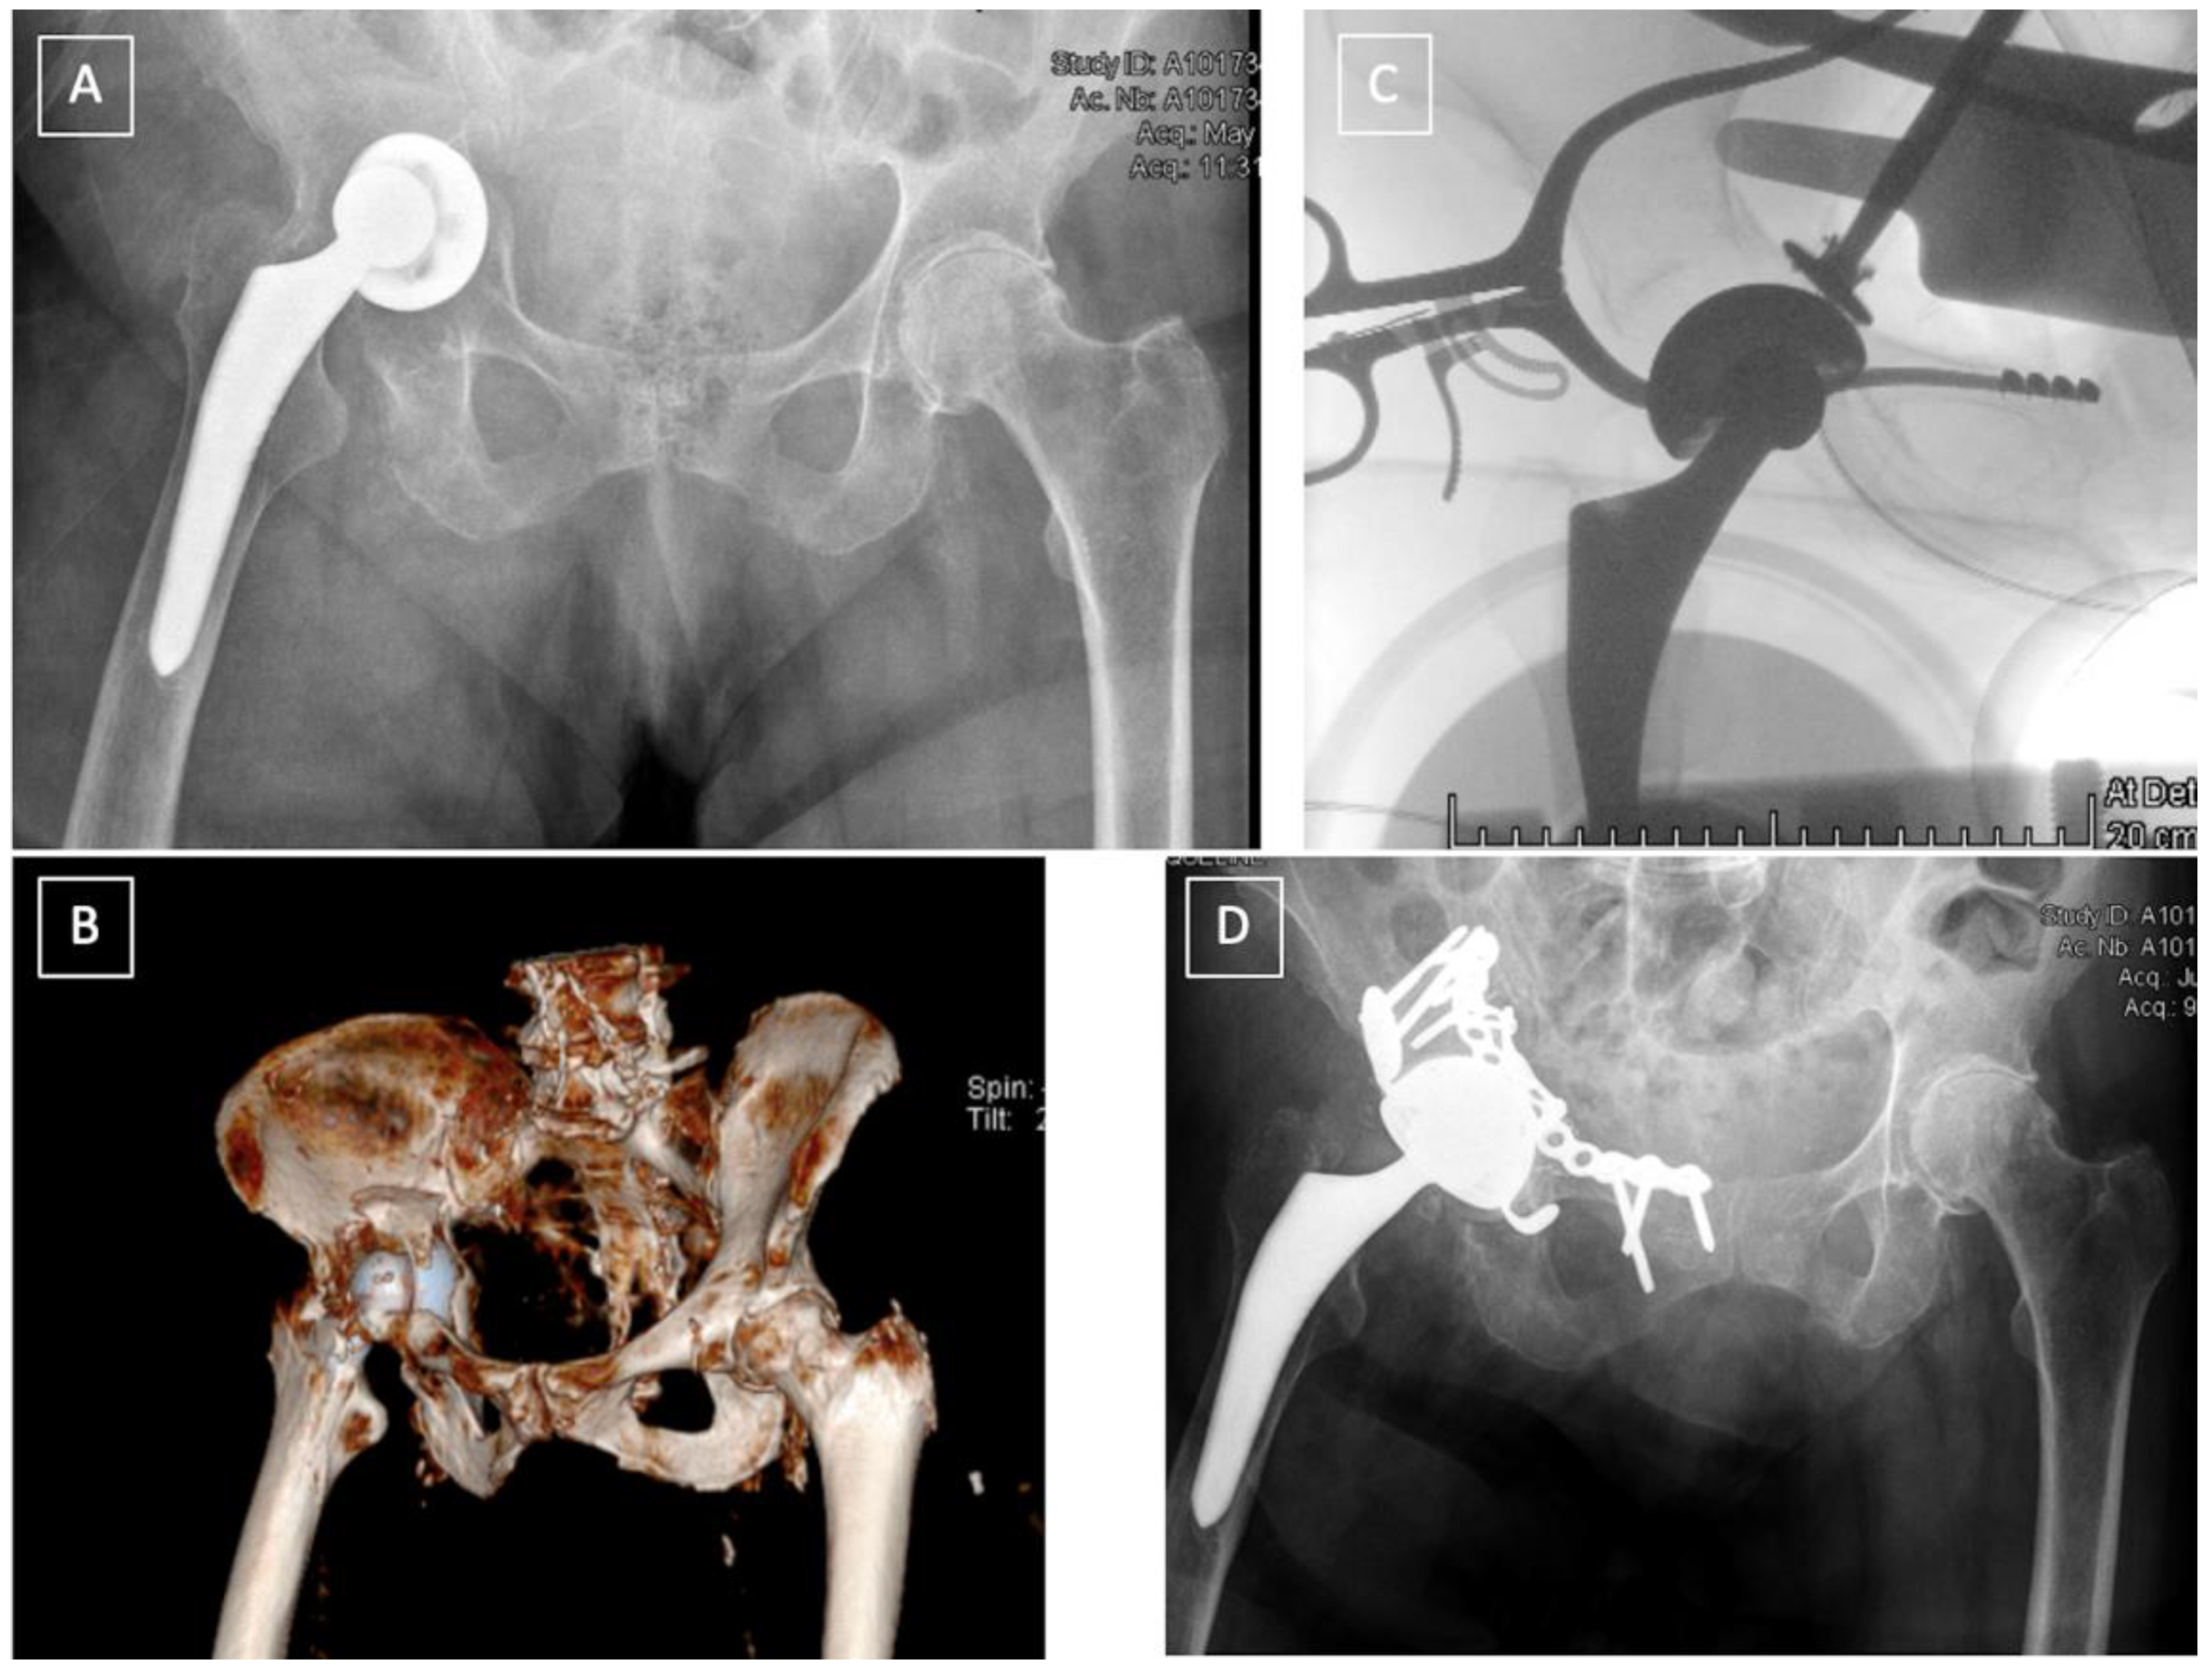

4.3. Pelvic Discontinuity (PD)

- The “Cup-cage construct” technique, currently the most popular treatment of chronic PD [42], was first described by Hanssen and Lewallen in 2005 [44]. It consists of an ilio-ischial cage, placed over an uncemented highly porous metal cup. In a majority of the cases, “jumbo cups”, defined by von Roth et al. [45] as an acetabular component with an outside diameter ≥66 mm in men and ≥62 mm in women, are used and thus help restore the centre of rotation (COR) of the hip in an anatomic position [46,47]. Remaining bone defects can be filled with augments or allograft. The cage offers initial stability and allows the osteointegration of the acetabular component. A polyethylene liner is then cemented in the cage in the correct position. Advantages of this technique are its favourable outcomes and high survival rates, ranging from 75–100% [37,42,48,49,50,51,52]. The main complications of this technique are dislocation (7–8%), infection (4–7%) and aseptic loosening (4–15%) [37,42,48,49].

- Acetabular distraction was first described by Sporer et al. in 2012 [53]. The acetabulum is reamed until the antero-superior and postero-inferior margins are engaged. Remaining bone defects are filed with porous tantalum augments. An acetabular component of the same material, 6–8 mm larger than the last reamer is then impacted. The distraction creates a press fit and a pelvic recoil as a result of ligamentotaxis [54]. The latter in conjunction with multiple screws inserted in the remaining ilium and ischium provides initial stability. The polyethylene liner or a dual mobility cup is then cemented into the shell [53]. Although relatively new, acetabular distraction is a promising treatment for chronic PD. Excellent results [40,42,53,55], with low complication rates, 3–5% aseptic loosening [40,53], have been reported at 2- to 7-year follow-up.